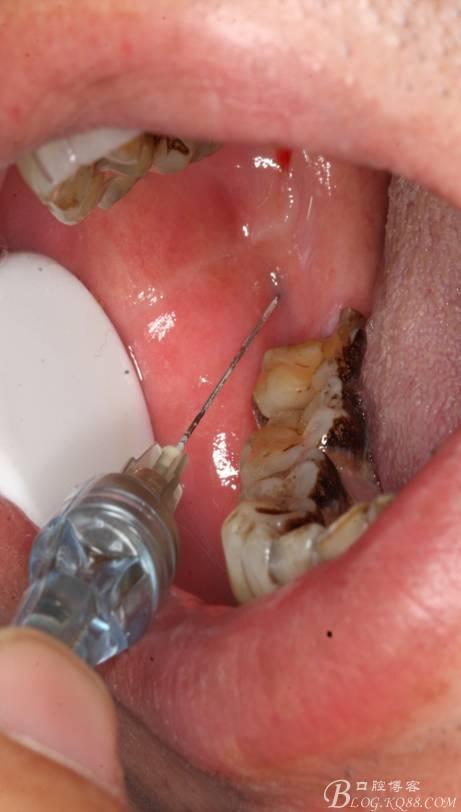

2.切開翻瓣

3.去骨、暴露48.